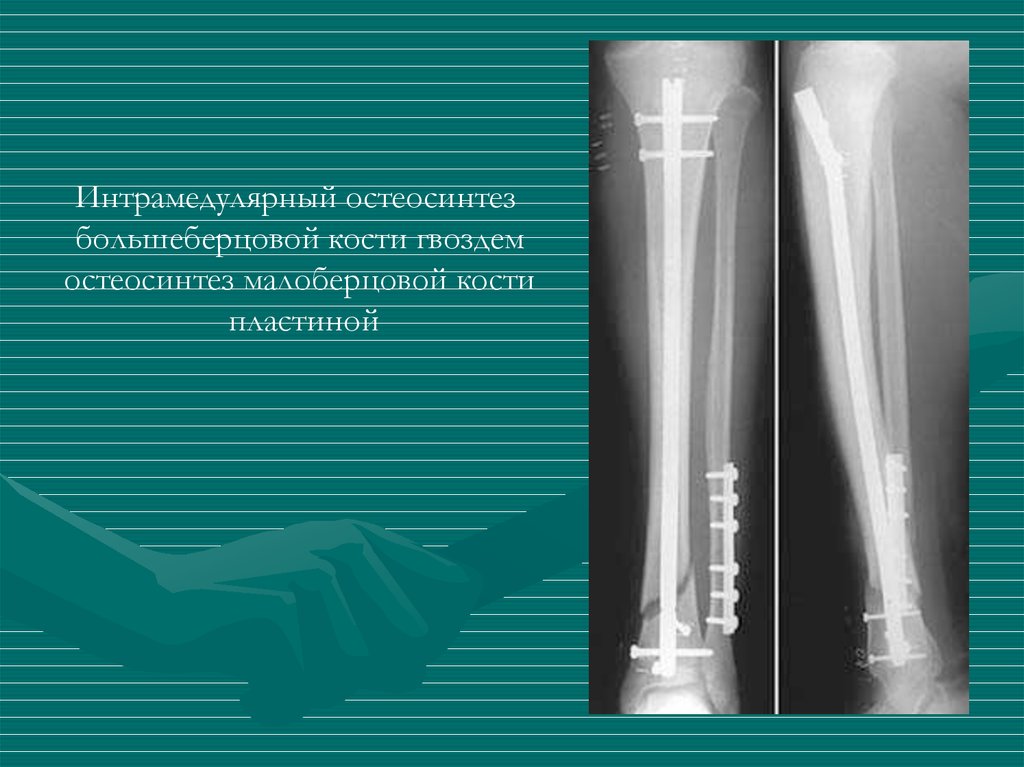

Интрамедулярный остеосинтез

большеберцовой кости гвоздем

остеосинтез малоберцовой кости

пластиной